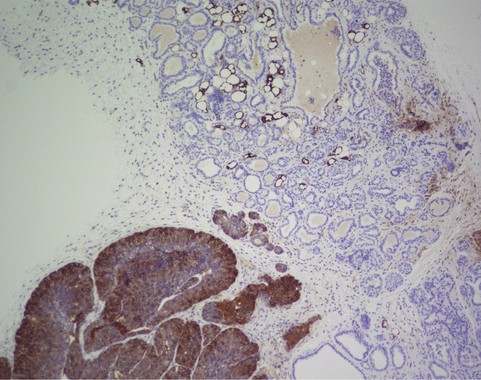

Imagen de inmunohistoquímica de FASN en una mama de ratón transgénico que desarrolla tumores de mama. En marrón oscuro, las zonas donde FASN está presente desarrollan tumores. En azul, ductos mamarios normales sin FASN y sin tumor. (Foto: CNIO)

“En nuestro modelo de ratón que desarrolla un cáncer de mama muy penetrante, las zonas en las que hay FASN sí desarrollan cáncer, mientras que en las zonas donde lo bloqueamos no llegaron a generarse tumores y la supervivencia aumentó en un 68 %”, dice Quintela. “Pero cuando tratamos de inhibir FASN con los tumores ya establecidos, hubo un pequeño efecto transitorio que casi no afectó a la progresión”.